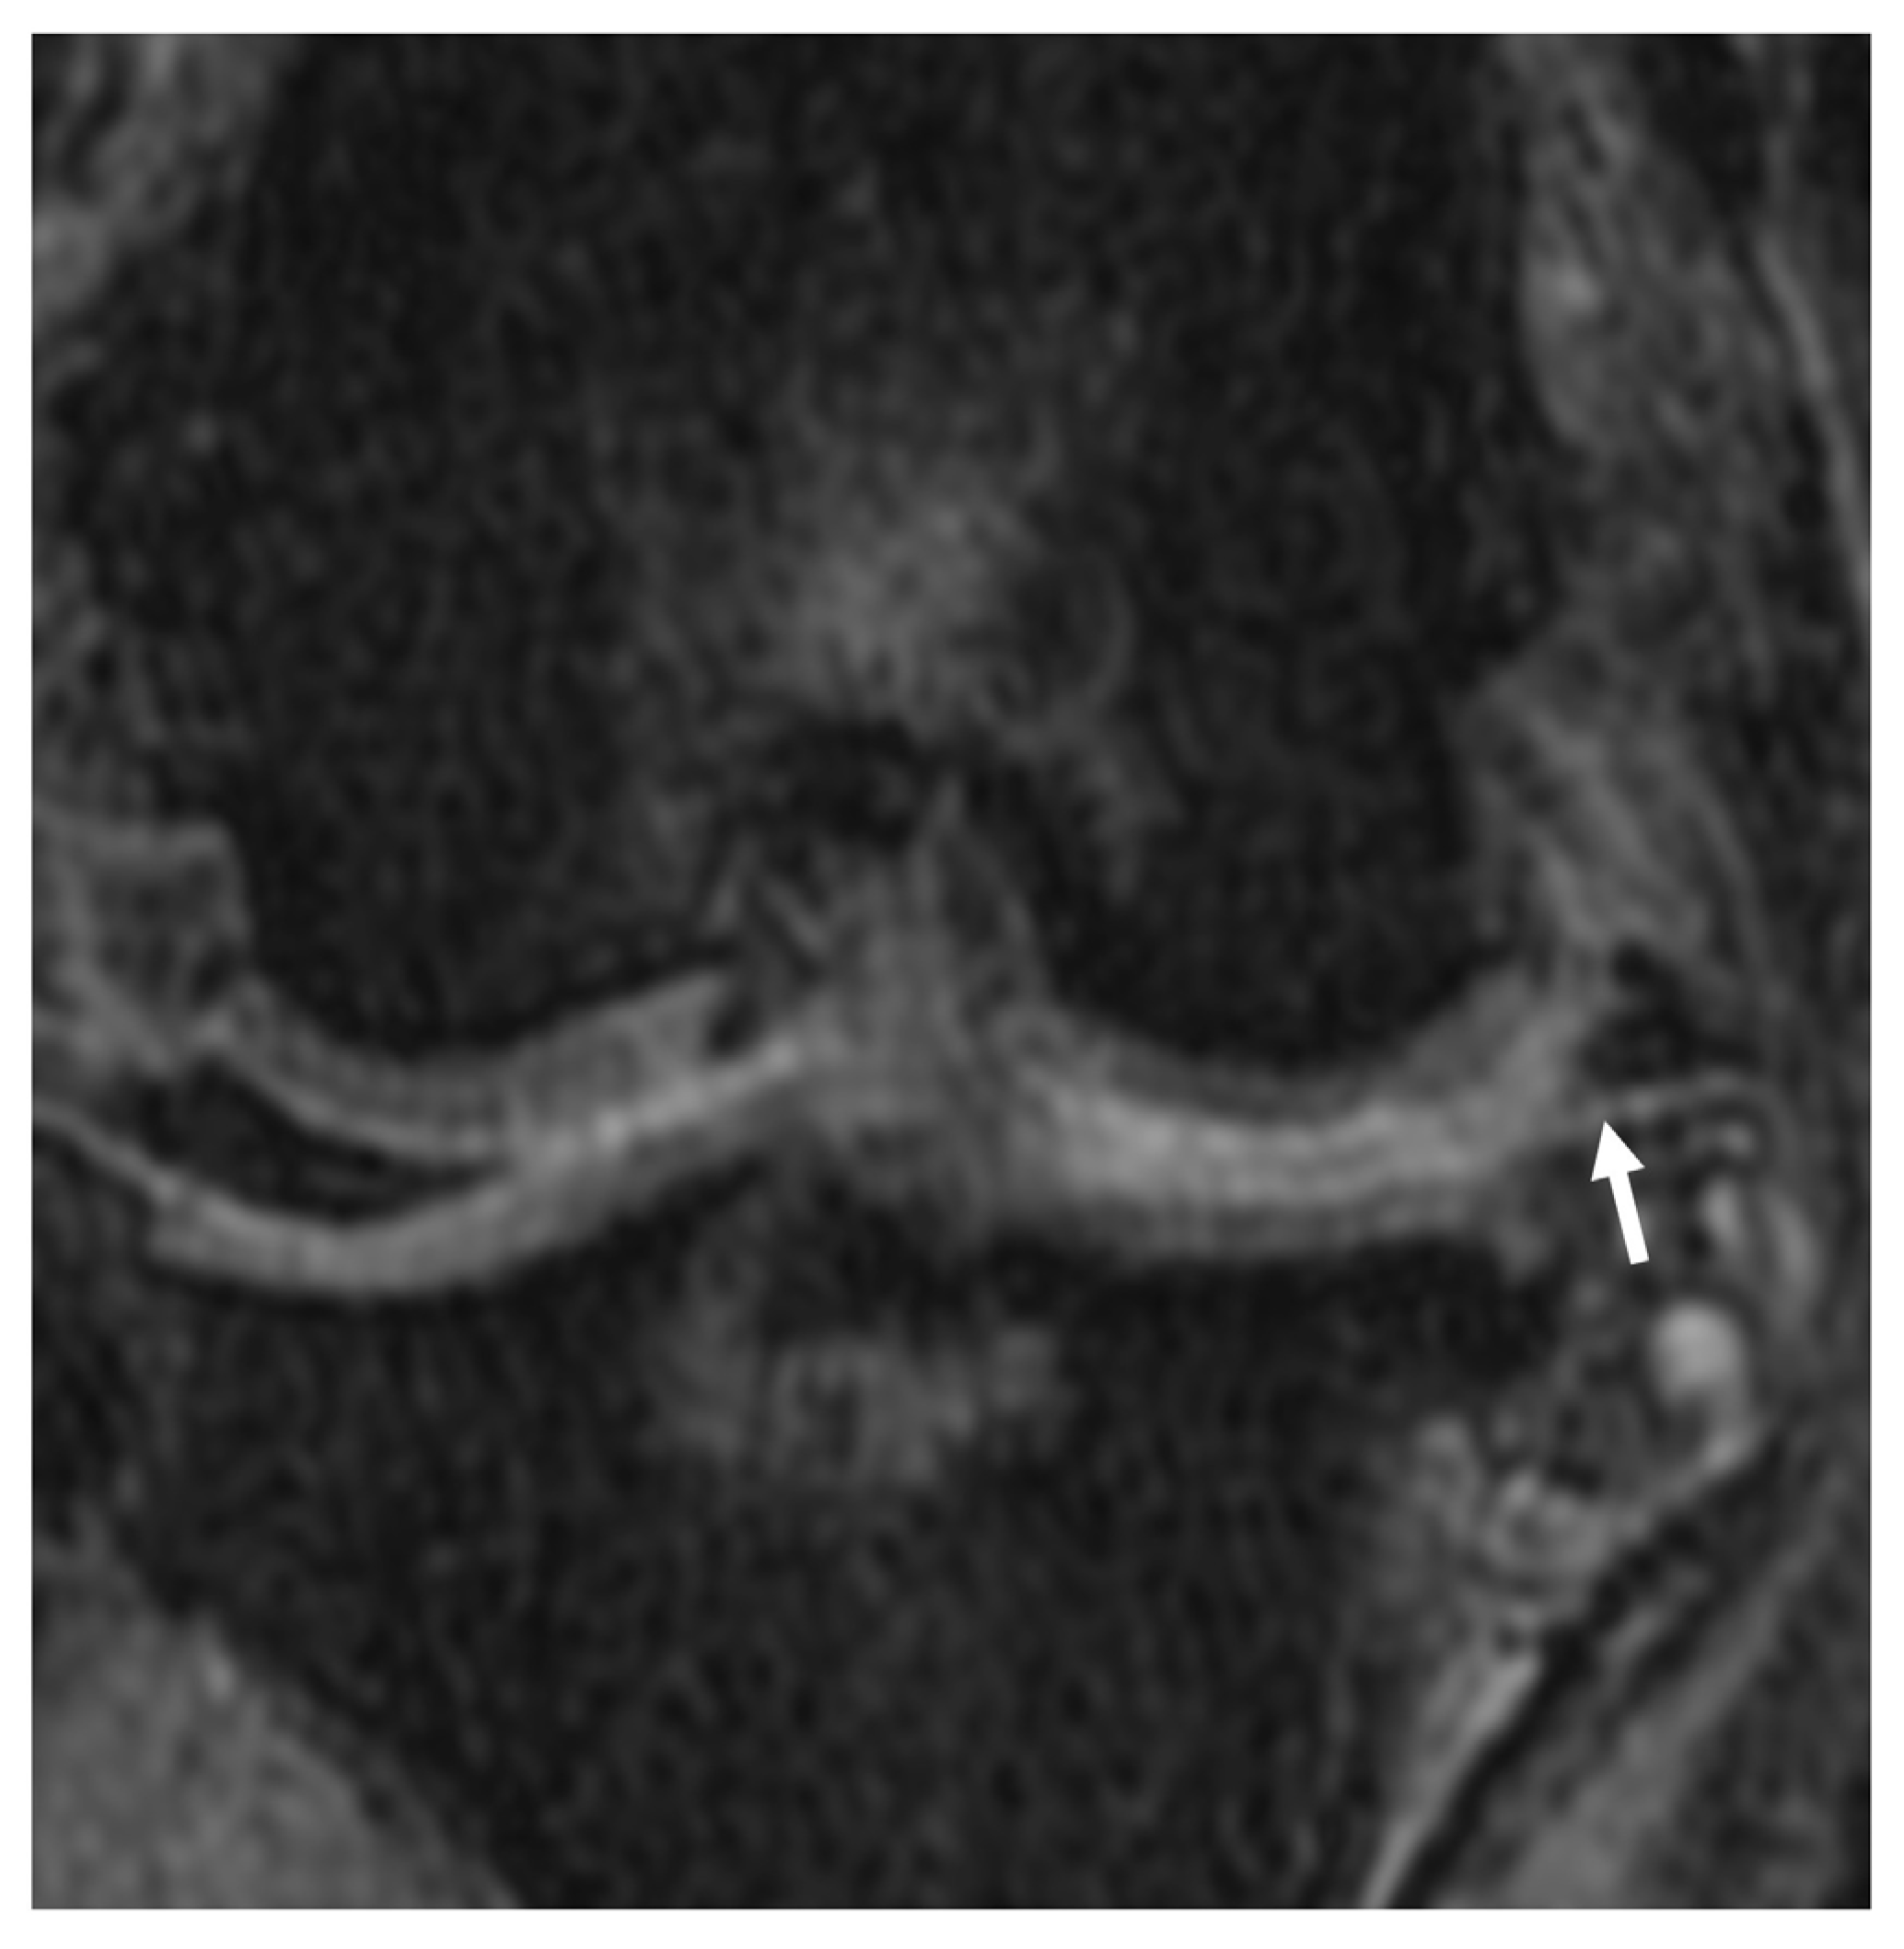

3.2.3. Synovial Effusion and Membrane Thickening

3.2.4. Subchondral Bone Lesions